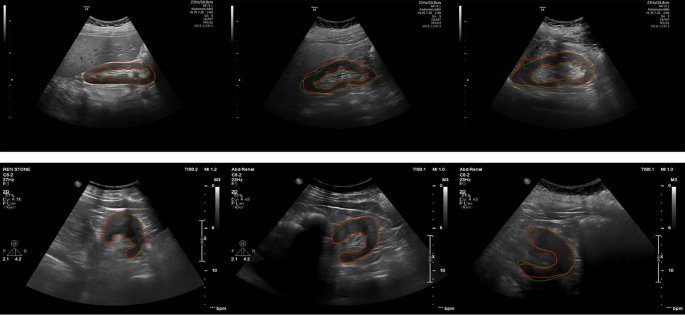

Figure 4 shows the results of the segmentation network on ultrasound images of the kidney in sagittal and axial views. In this Figure, the green contour shows the ground truth that an expert delineates, and the red contour depicts the predicted mask by the proposed network. The promising agreement between the manual and automatic contour proves the robustness of the proposed method.

Segmentation results of the ultrasound kidney in the sagittal (top row) and axial (bottom row) images. The green contours represent the manual segmentation and the red contours represent automatic results.